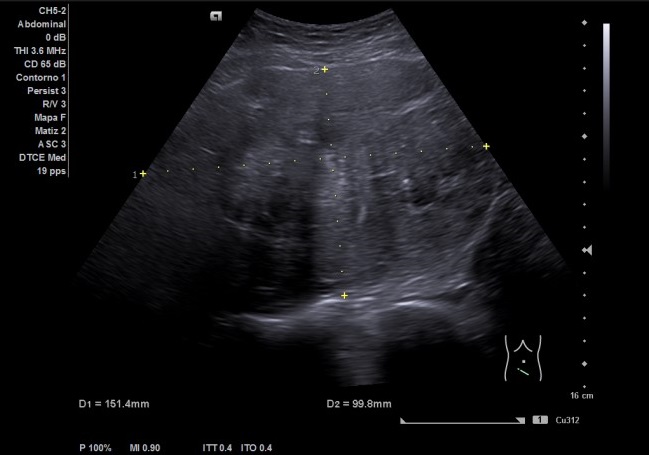

Riñón derecho ligeramente aumentado de tamaño con aparente hidronefrosis grado 1-2.

Riñón izquierdo tamaño y ecoestructura normal. Se visualiza vejiga con paredes homogéneas y ambos jets. Útero en anteversión, con mioma de 15,14 x 9,98 cm. Anejos normales.